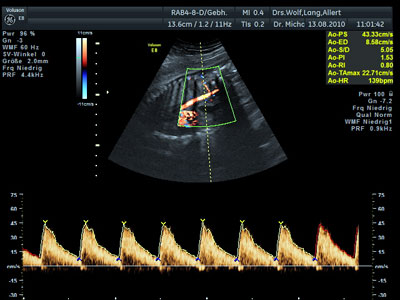

Mit Hilfe des Ultraschalls können eventuell vorhandene Entwicklungsstörungen und Fehlbildungen des Kindes frühzeitig erkannt werden und so rechtzeitig notwendige Therapien und erweiterte Diagnostik eingeleitet werden. Es lassen sich mit unseren modernsten Ultraschall-Geräten auch Doppler-Untersuchungen durchführen, die Hinweise auf eine Plazentafunktionsstörung geben können.